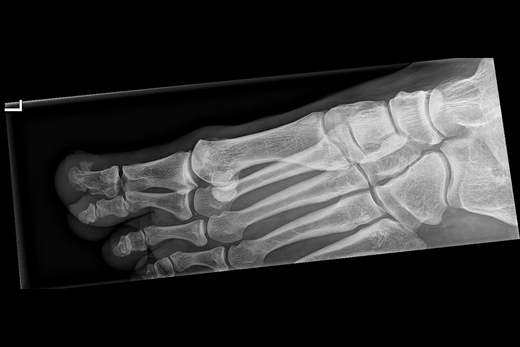

Twee patiënten bezoeken kort achter elkaar de huisarts, omdat ze een zwelling onder een nagel hebben. Na onderzoek blijkt het te gaan om een subunguale exostose, een zwelling onder de nagels van tenen of vingers. Vanwege de zeldzaamheid van deze aandoening duurt het enige tijd voor de huisarts de diagnose stelt. Wat moet u doen bij een patiënt met een zwelling onder de nagel?